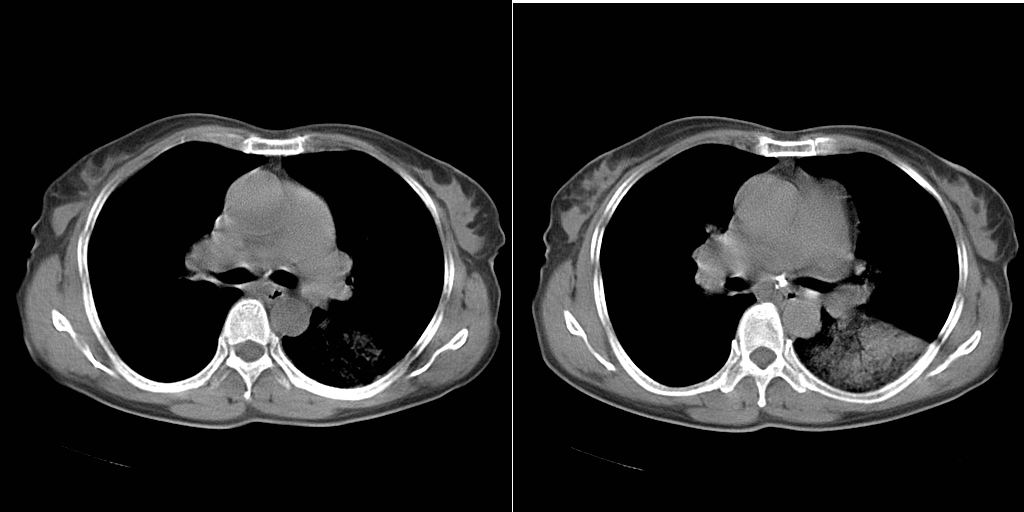

以下是引用dyqct在2007-1-23 15:01:00的发言:[br]左肺下叶实变、略萎陷,近肺门下部密度不均。上腔静脉后及隆突前见肿大淋巴结。余未见异常。[br]考虑:1、左肺下叶中心型肺癌伴肺不张、纵隔淋巴结转移;[br] 2、建议增强扫描并做任意平面重建确定肿块范围及支气管受累情况。

以下是引用同在2007-1-23 19:59:00的发言:[br]左肺下叶中央型肺癌伴肺不张及纵隔淋巴结转移.